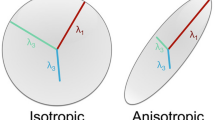

Additionally, when measuring development, DTI parameters suffer from partial volume effects owing to free-water contamination and complex fibre orientations in the immature brain (Lynch et al. 2020). Thus, to investigate the development status of SLF sub-bundles from a more precise microstructural perspective, some new technologies should be applied to analyse high-quality diffusion images during the foetal and neonatal periods. Neurite orientation dispersion and density imaging (NODDI) is a multi-compartment model that can overcome these limitations, and it has high specificity to characterize the microstructural features of WM development. Specifically, in WM, NODDI can differentiate three tissue types in a voxel: (1) the intra-neurite compartment, referring to the space bounded by the membrane of axons that enables quantitative measures of the packing density and myelination of axons, termed the neurite density index (NDI), and the orientation coherence of neurites, termed the orientation dispersion index (ODI); (2) the extra-neurite compartment, referring to the space around the axons, which is occupied by oligodendrocytes; and (3) the free-water compartment, mainly representing cerebrospinal fluid (CSF) (Zhang et al. 2012; Lynch et al. 2020). The NODDI microstructural parameters may provide unique insight into the complex development of WM tracts and provide complementary information to that provided with DTI.